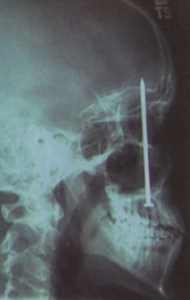

Doslova hrobníkovi z lopaty utekl nedávno třicetiletý rakouský tesař. Tomasovi Schoenitzovi vnikl do hlavy deseticentimetrový hřebík a jako zázrakem nepo?kodil ?ivotně důle?itá centra v jeho mozku. Podle zpravodajského serveru Ananova prý posti?eného dělníka dokonce ani nebolela hlava.

Krátce před nehodou Schoenitz pracoval na stře?e jednoho domu v Salcburku, kde se nechtěně srazil s kolegou dr?ícím v ruce nastřelovač hřebíků. Hlavou se přitom dotkl přímo ústí pistole, čím? spustil střelný mechanismus a ne?těstí ji? ne?lo nijak zabránit.

První pomoc dorazila na místo za pár minut. ?okovaným zdravotníkům rychlé záchranné slu?by tesař sdělil, ?e se cítí v rámci mo?ností dobře. Lékaři jej ihned převezli do nemocnice, kde mu neurochirurgové po devadesátiminutové operaci vyňali hřebík z mozku. ?Mu? měl ohromné ?těstí, ?e vůbec pře?il," uvedl po zákroku doktor Alois Karlbauer ze salcburské nemocnice.